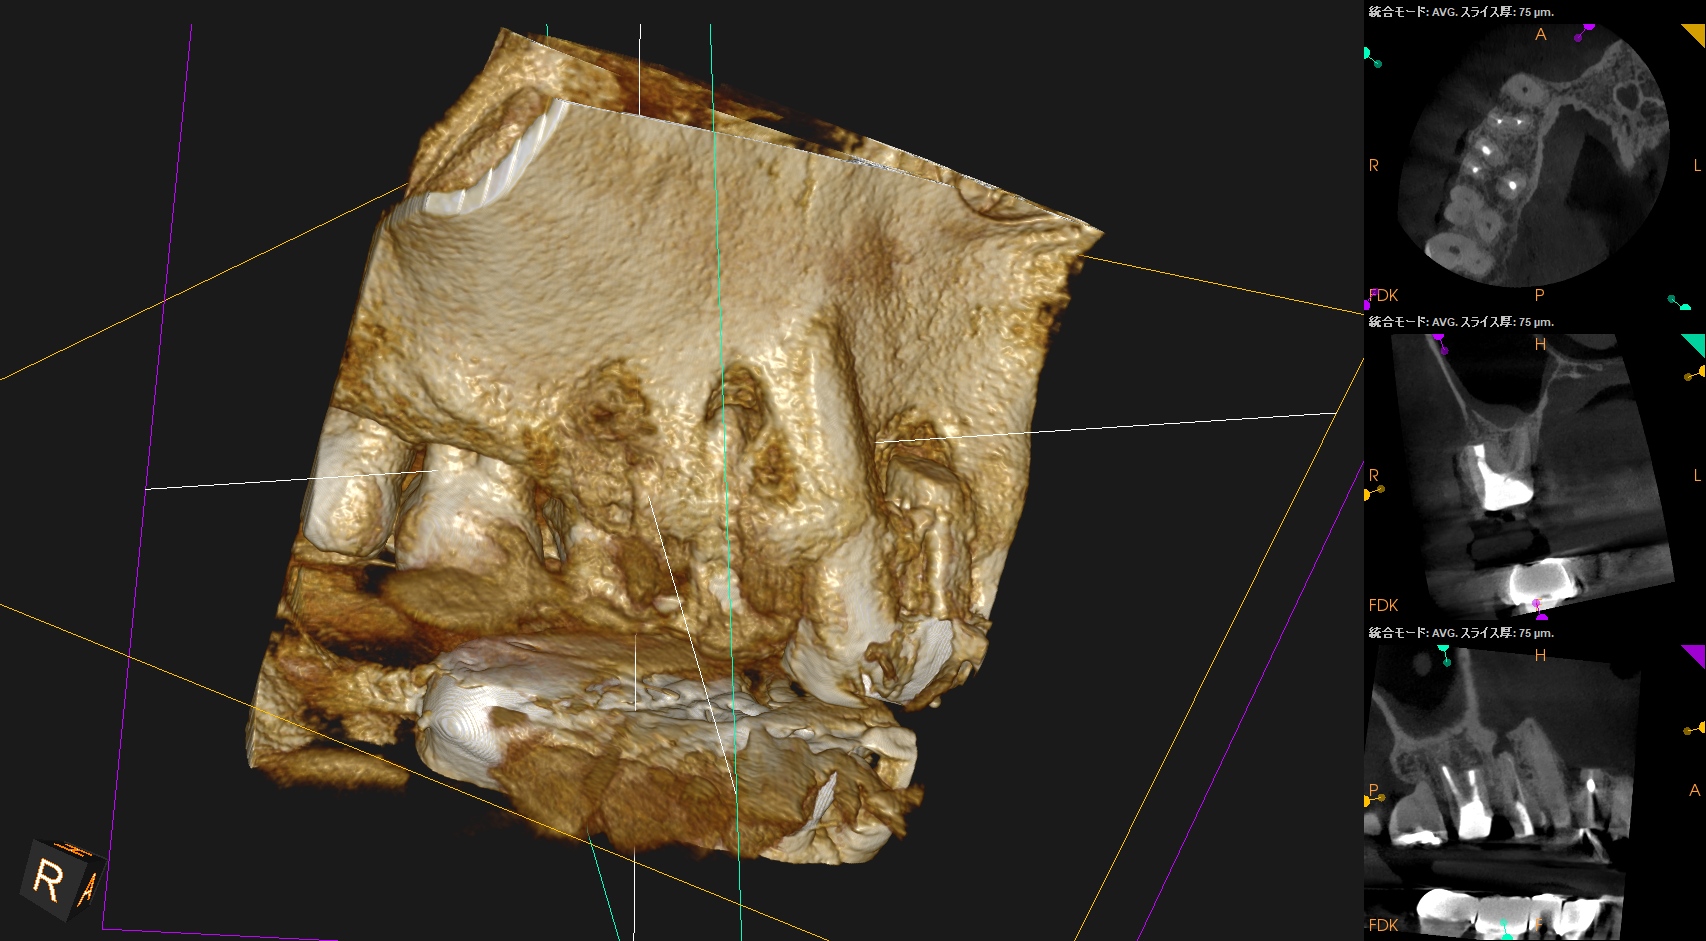

治療前の予測としては以下だ。

CEJよりも13mm先にApexがある。

が、この際にOsteotomyを行わなくてもApexには辿り着ける。

そしてApexから3mmで切断した時に、頬舌的には4.4mm削るだけで済む。

Very easyな外科治療だ。

そしてその際、Gutta PerchaがMBの中心にあることからこの根管は1根管であるということまでわかる。

まさにSuper easyなApicoectomyである。

このように

見れる・わかる・映りがいいCarestream社のようなCBCTがあれば, ここまで術前に予測ができるのである。